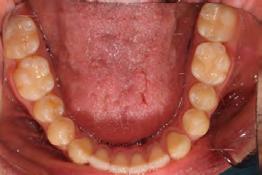

Clinical evaluation showed a mild Class III skeletal pattern with a constricted maxilla, mildly dolichofacial and straight

profile (Figure 1). Full adult dentition was present with all third molars extracted. Maxillary and mandibular incisors were normoclined. The maxillary midline coincided with the facial midline, and the mandibular midline was 2 mm to the right of the facial midline. There was a 2 mm to 5 mm lateral open bite on the right side from the second molar to the lateral incisor, and the maxillary occlusal plane was canted to the left of the interpupillary line. A lateral tongue thrust into the open bite was noted on swallow.

The right side was in posterior crossbite and there was an edge-to-edge anterior bite with wear on the maxillary central incisors. Mild gingival recession was noted, but soft tissue was generally within normal limits. CBCT analysis found no radiographic evidence of osteoarthritis in the TMJ joints, nor osseous or apical pathology involving the maxillary or mandibular teeth. His airway was not constricted. Initial report from the myofunctional therapist indicated that the patient never developed a mature swallow sequence and had a bilateral posterior tongue thrust.

Figure 1. Initial records.